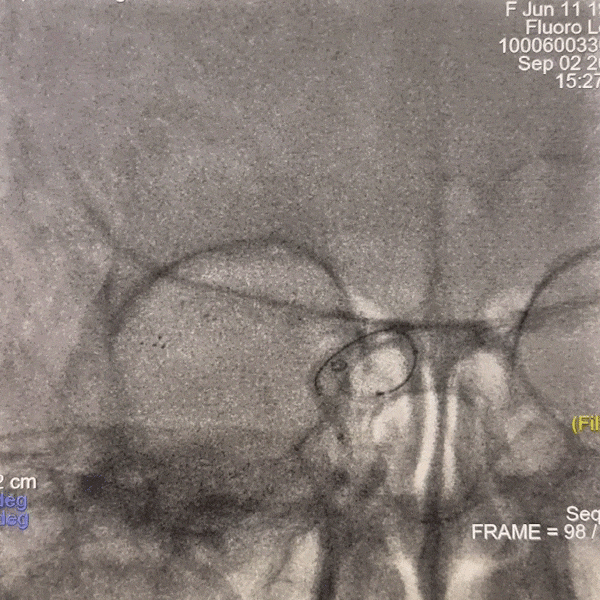

通路建立:右侧远桡动脉置鞘成功,5F多功能导管尝试超选右侧颈总动脉失败。

撤出多功能导管和短鞘,交换088输送导管至右侧锁骨下动脉近端,沿输送导管送入赛诺神畅APEX TRA GC™5F-130cm SIM2至主动脉弓,成袢后轻松超选入右侧颈总动脉,同轴沿SIM2导管将输送导管送入右侧颈总动脉,撤出SIM2导管,沿导丝将6F 115cm远端通路导管送至右侧颈内动脉C4段。

动脉长鞘怎么置入一技之“长”丨经桡及经股困难入路应用赛诺神畅APEX TRA GC™导引导管建立通路病例合集_https://www.jmylbn.com_新闻资讯_第33张

路图下上导丝、导管

动脉长鞘怎么置入一技之“长”丨经桡及经股困难入路应用赛诺神畅APEX TRA GC™导引导管建立通路病例合集_https://www.jmylbn.com_新闻资讯_第34张

SIM2导引导管超选右侧颈总动脉

动脉长鞘怎么置入一技之“长”丨经桡及经股困难入路应用赛诺神畅APEX TRA GC™导引导管建立通路病例合集_https://www.jmylbn.com_新闻资讯_第35张

跟进输送导管

动脉长鞘怎么置入一技之“长”丨经桡及经股困难入路应用赛诺神畅APEX TRA GC™导引导管建立通路病例合集_https://www.jmylbn.com_新闻资讯_第36张

交换远端通路导管

后撤微导管至右侧大脑中动脉M1段分叉处,路图下微导丝超选入右侧大脑中动脉M2段上干,跟进微导管,撤出微导丝,手推造影显示微导管在血管真腔内,再次送入微导丝,撤出微导管,沿微导丝送入2.0*15mm 球囊扩张导管,由远及近分次进行扩张,扩张后显示狭窄段较前明显好转。

撤出微导丝,沿球囊扩张导管送入4.5*14mm 支架,精确定位后缓慢释放支架。

动脉长鞘怎么置入一技之“长”丨经桡及经股困难入路应用赛诺神畅APEX TRA GC™导引导管建立通路病例合集_https://www.jmylbn.com_新闻资讯_第44张

释放支架